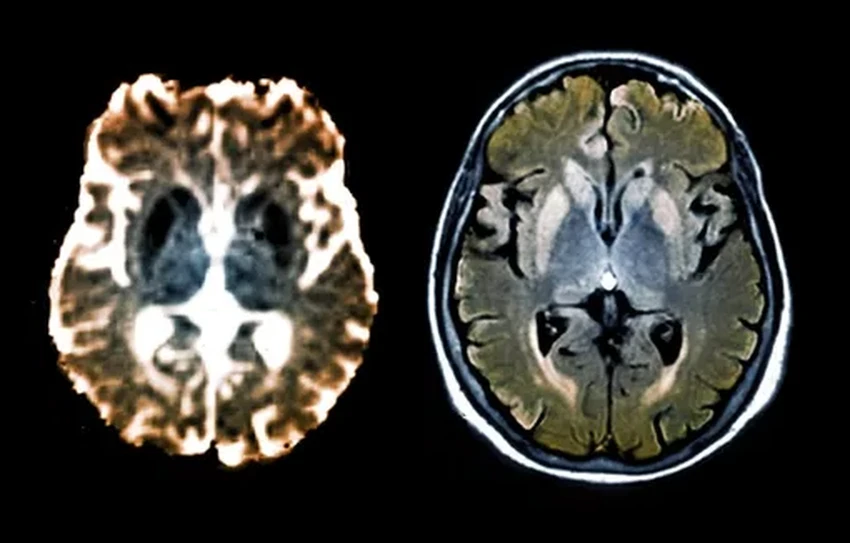

Многие нейродегенеративные болезни — Альцгеймера, Паркинсона — это, по сути, трагедия на молекулярном уровне. Гены сбиваются с ритма и начинают штамповать белки с фатальными ошибками. Эти белки-уродцы засоряют и убивают нейроны. Но что, если просто остановить этот бракованный конвейер, не трогая сам чертёж — ДНК? Природа знает этот трюк и использует его постоянно — через процесс метилирования. Исследователи просто направили этот природный механизм точно в цель: заставили гены, производящие смертельные прионы, замолчать. Просто и гениально.

Когда CHARM доставили в мозг мышей, результат превзошёл ожидания: производство рокового белка PrP упало более чем на 80% по всему мозгу. Это намного выше минимального порога, необходимого для терапевтического эффекта! А после выполнения миссии CHARM, словно агент-невидимка, самоуничтожается, не оставляя следов в клетке. Идеальный инструмент.

Перспективы? Огромные. Вайсман уверен, что CHARM можно адаптировать для борьбы с другими белковыми «засорениями» — при болезни Паркинсона и Альцгеймера. «Мы знаем, что эпигенетическое "заглушение" работает для большинства генов», — говорит он. Похоже, мы научились не ломать систему, а просто нажимать правильные кнопки. И это меняет всё.